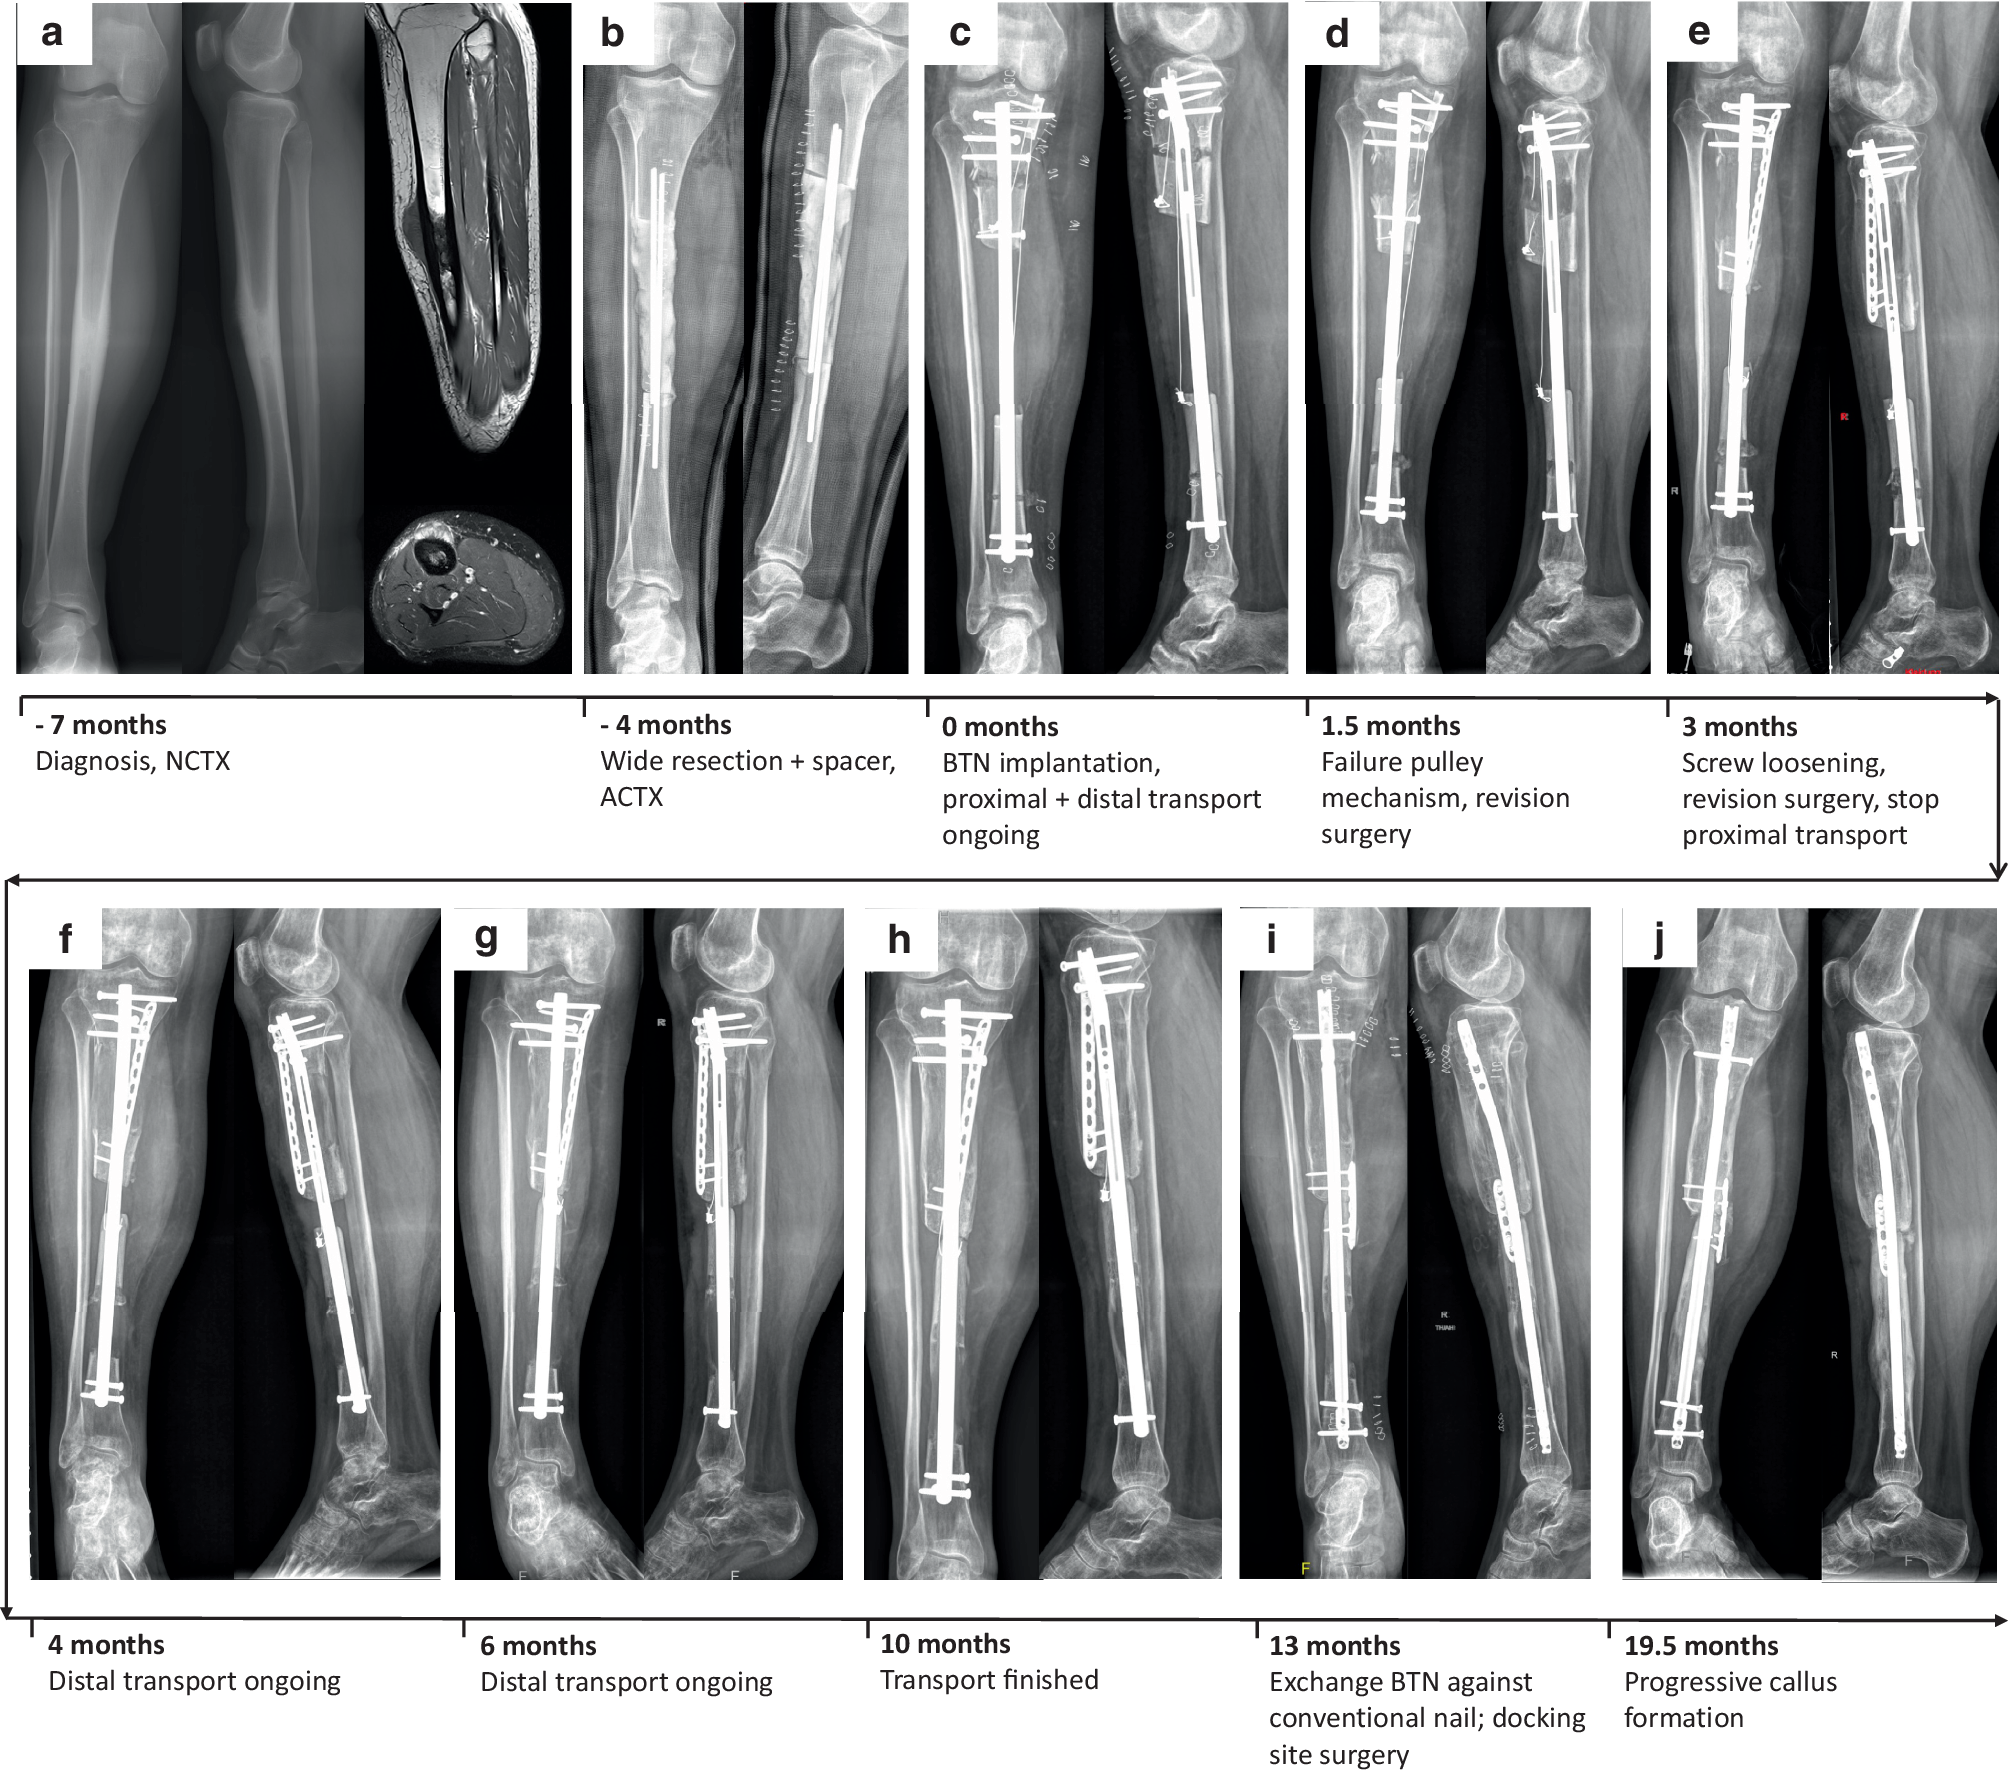

An 18-year-old male patient with Ewing’s sarcoma of the right tibial diaphysis underwent wide resection with clear surgical margins following 9 cycles of neoadjuvant CTX. A temporary spacer was implanted in the bony defect measuring 14.1 cm until completion of 5 adjuvant CTX cycles (Fig. 1a, b). Thereafter, a two-level tibial osteotomy was performed and a BTN 11.5/360 mm implanted. To shorten the transport period, a combined proximal and distal bone transport via a pulley mechanism was constructed (Fig. 1c). For this purpose, a wire was fixed to the proximal fragment, rerouted over a screw secured with a mini-plate in the proximal healthy bone, and again fixed at the distal fragment (Fig. 1c). By redirecting the force emerging from transport of the proximal fragment downwards, the distal fragment is pushed upwards. Following surgery, the patient was allowed 40 kg partial weight bearing. The pulley mechanism for retrograde transport of the distal segment failed 1.5 months after surgery, necessitating revision surgery (Fig. 1d). During this procedure, the simultaneous double osteotomy system was abandoned, aiming at enabling completion of proximal bone segment transport via the screw. In a second procedure 1.5 months later due to screw loosening (Fig. 1e), the proximal segment was fixed with a plate and a retrograde bone segment transport reinitiated via renewed osteotomy of the distal segment and a cable-wire pulley mechanism. Bone segment transport was completed after 10.3 months (Fig. 1f–h). Subsequently, the BTN was exchanged with a conventional tibial nail (Expert Tibial Nail, DePuy Synthes, Johnson&Johnson Medical Products GmbH, Vienna, Austria) and the proximal docking site was prepared with curettage and plate fixation due to the lack of complete consolidation (Fig. 1i). Thereafter, the patient was allowed full weight bearing. At latest follow-up 19.5 months after the start of bone transport, complete and partial bony consolidations (confirmed by CT scan) were present at the distal and proximal segments, respectively (Fig. 1j). The patient was fully weight bearing without any pain and had no evidence of disease.

Fig. 1

Clinical course of patient 1 (18-year-old male patient with Ewing’s sarcoma of right tibial diaphysis. Images of patient 1 showing (a) preoperative x-rays in anterior-posterior (a.p.) and lateral planes together with two magnetic resonance imaging (MRI) scans in sagittal (top) and axial (bottom) of the right tibia. X-ray images in a.p. and lateral planes following wide resection and spacer implantation (b), directly after implantation of the bone transport nail (BTN; c), at 1.5 months following BTN implantation when the pulley mechanism failed (d), at 3 months when another revision surgery due to screw loosening became necessary (e), at 4 (f) and 6 months (g) with bone transport ongoing, at 10 months with finished bone transport (h), at 13 months when the BTN was exchanged against a conventional nail (i), and at last follow-up (19.5 months) when progressive callus formation was visible, but no complete bony consolidation had taken place (j). (ACTX adjuvant chemotherapy, BTN bone transport nail; NCTX neoadjuvant chemotherapy)